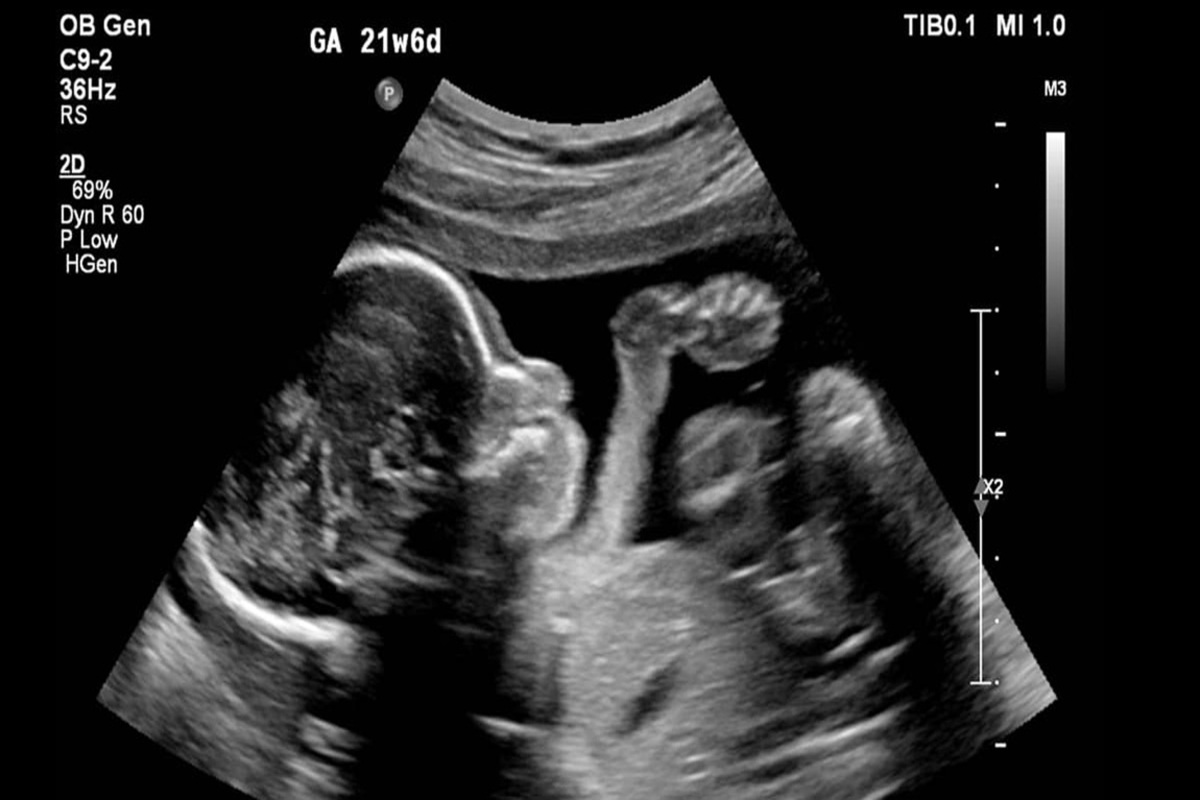

کیهان: زنان با چه استدلال هایی حاضر به سقط جنین می شوند؟

کیهان نوشت: بر اساس پژوهشی که پژوهشکدة علوم بهداشتی جهاد دانشگاهی انجام داده، به دست آمده که مشکل مالی و اقتصادی، اختلاف با شوهر، جنسیت جنین، فاصلة کم بین بارداری‌ها، سن کم مادر، سن بالای مادر، تعداد زیاد فرزندان، گرفتاری شغلی مادر، اعتیاد شوهر، بارداری در ابتدای ازدواج یا در دوران عقد و... از عواملی هستند که در بارداری ناخواسته، سبب می‌شوند که مادر تصمیم به سقط جنینش بگیرد.